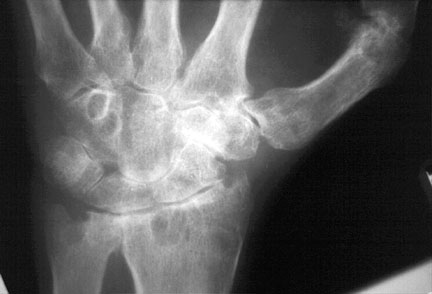

Tymczasem coraz więcej reumatologów wykorzystuje USG do leczenia schorzenia. U większości chorych z RA w remisji klinicznej dołączyło się zapalenie, a aktywność mocy Dopplera jest łączona z radiograficzną progresją oraz zaostrzeniem.

Zdaniem badaczy, USG odgrywa role w diagnozowaniu oraz przy iniekcjach dostawowych, ale przy ocenie aktywności zapalnej terapia pod kontrolą USG nie jest uzasadniona opierając się na uzyskanych wynikach.